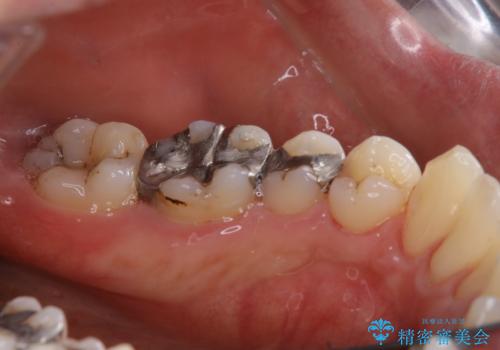

歯の表面に、茶色く色が残っている所がありますが、これは詰め物の変色によるものです。以前に、CR(コンポジットレジン)による虫歯治療がされています。

CRは経年的劣化や、着色してしまうことがあります。PMTCでクリーニングを行うと、古いCRが目立つことがあるため、気になる際は詰め替えを行います。

茶色くなっている部分が、着色なのか、劣化なのか、虫歯によるものなのかは判別が難しいことがあります。そのため、定期的にPMTCを行うことで状態の確認が的確に行えます。